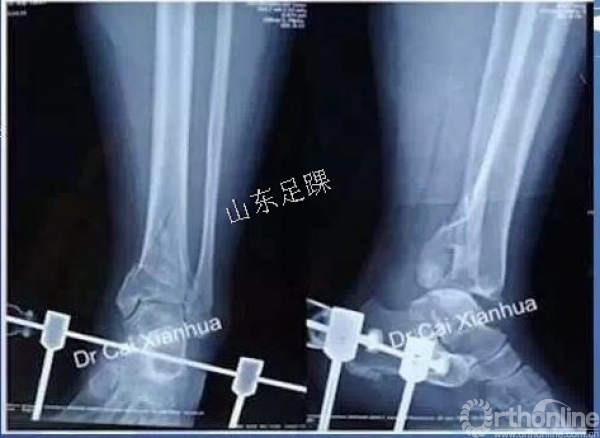

(1)外架指征:软组织情况不良;骨折粉碎、骨缺损;多发伤;存在手术禁忌。

大部分作为分期治疗的首期治疗。外架固定针一定要超出内固定钢板的位置(钢板不能跨外架固定针固定,增加感染机率)。

(2)方法:闭合复位后石膏固定、跟骨牵引(6~8周)、外固定器固定。